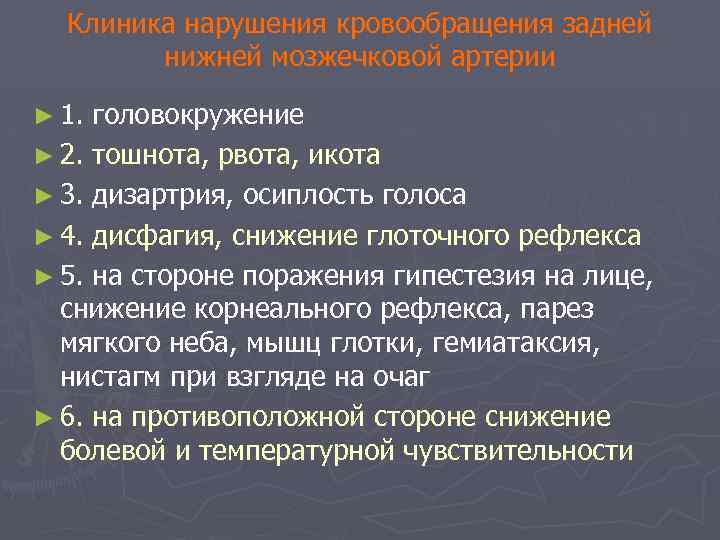

Клиника нарушения кровообращения задней нижней мозжечковой артерии ► 1. головокружение ► 2. тошнота, рвота, икота ► 3. дизартрия, осиплость голоса ► 4. дисфагия, снижение глоточного рефлекса ► 5. на стороне поражения гипестезия на лице, снижение корнеального рефлекса, парез мягкого неба, мышц глотки, гемиатаксия, нистагм при взгляде на очаг ► 6. на противоположной стороне снижение болевой и температурной чувствительности